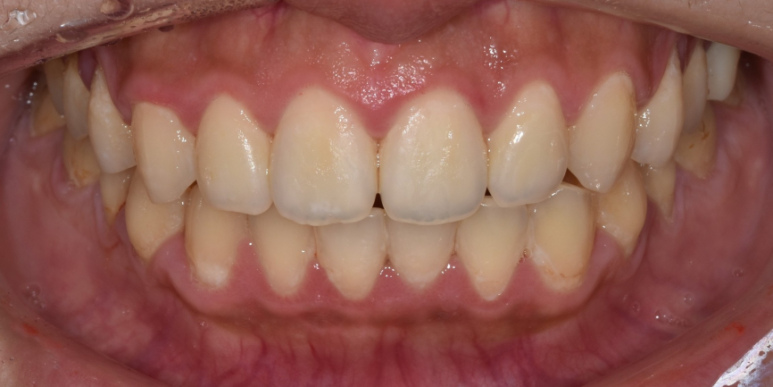

왜소치가 고민이 되어 본원에 내원하셨던 환자분의 사례입니다.

왜소치는 정상치아보다 크기가 작은 치아를 말하며, 흔히 '대문니'로 표현되는 앞니 양옆 치아(상악 측절치)에 많이 나타나는데요.

잘 아시겠지만, 이 뾰족하고 작은 치아는 교정치료로는 개선하기 어렵습니다.

그래서 정상적인 치아 크기와 모양을 만들기 위해선 라미네이트 등의 심미보철치료를 고려해야 하는데요.

(전) 2022-01-20, (후) 2022-01-27

해당 환자분은 교정으로 치아배열은 고른 상태셨기 때문에 왜소치인 치아 1개만 라미네이트 시술을 진행하게 되었습니다.

치아 1개만 진행하기 때문에 기존 치아와 이질감이 없도록 자연스러운 색상으로 시술해 드렸는데요.

시술 후 환자분도 본인 치아 같고 감쪽같다며 매우 흡족해하셨던 사례입니다. ^^